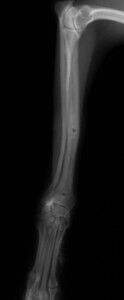

その後、1か月普通に生活していました。レントゲンを撮ったところ、骨は十分に増生していたので、心配ないと判断しプレートを取りました。プレート除去前

プレート除去後

プレート除去後は何の問題もなく生活しています。うまくいきました。